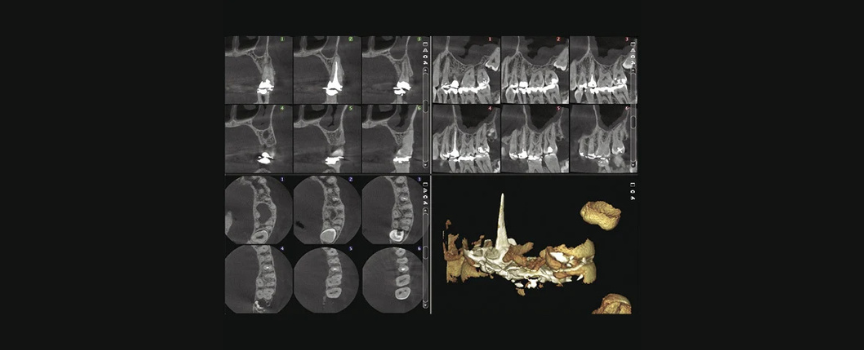

Obrazy Kliniczne Planmeca ProMax 3D s

Planmeca ProMax 3D s umożliwia swobodny dobór odpowiedniej rozdzielczości, wielkości woksela oraz wartości ekspozycji dostosowanych do Twoich aktualnych potrzeb. Urządzenie wykonuje obrazowanie 2D i 3D, a także obsługuje wiele innych opcji obrazowania.

Specjalny tryb obrazowania endodontycznego pozwala na tworzenie szczegółowych, trójwymiarowych zdjęć. Woksele o rozdzielczości 75 μm zapewniają wyjątkową jakość obrazu, uwzględniając nawet najdrobniejsze detale.